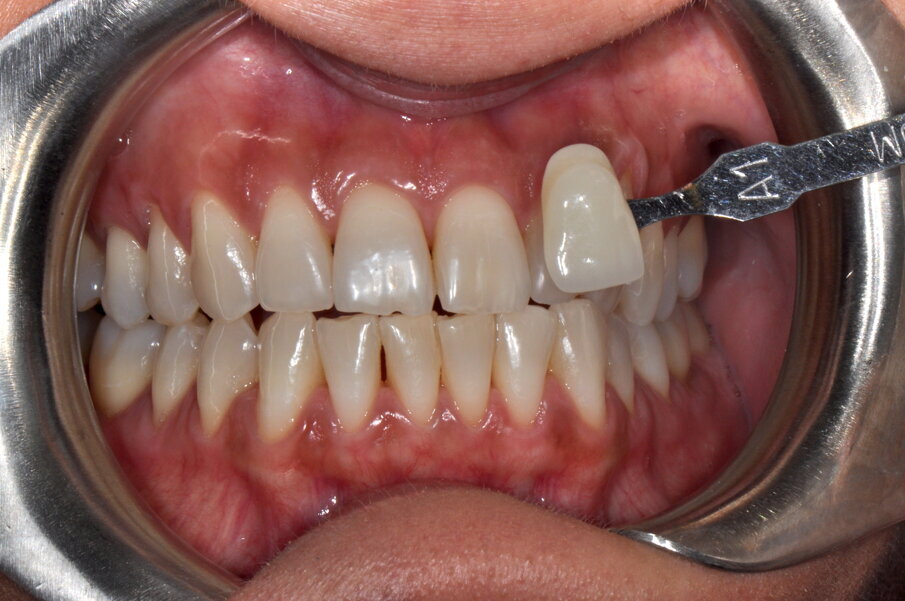

Fig. 5 - Stabilizzazione del colore ad una settimana.

Fig. 7 - Fotografia frontale scattata dopo la seduta di igiene professionale mediante l’utilizzo del sistema Airflow® Prophylaxis Master (EMS®) con polvere a base di eritritolo® e ablatore a ultrasuoni con punta perioslim (PS, EMS®).

Fig. 9 - Colore post sbiancamento professionale utilizzando la scala “Vita” A2.

Fig. 10 - Colore finale utilizzando la scala “Vita” A1.

I risultati ottenuti in questi due casi sono soddisfacenti sia dal punto di vista dell’operatore che, soprattutto, dal punto di vista del paziente che ha immediatamente percepito il cambiamento dichiarandosi felice e che ha suggerito a diversi amici la stessa procedura. È chiaro che risultati simili sono ottenibili su pazienti senza ricostruzioni o lavori protesici nel settore estetico e con buona compliance domiciliare sia nella rimozione della placca sopra-gengivale sia nel seguire le indicazioni post trattamento relative alle sostanze da evitare o limitare e all’eliminazione del fumo. I richiami di igiene professionale semestrali si rendono necessari per supportare il paziente, per rimuovere le macchie estrinseche e per verificare la stabilità del risultato.